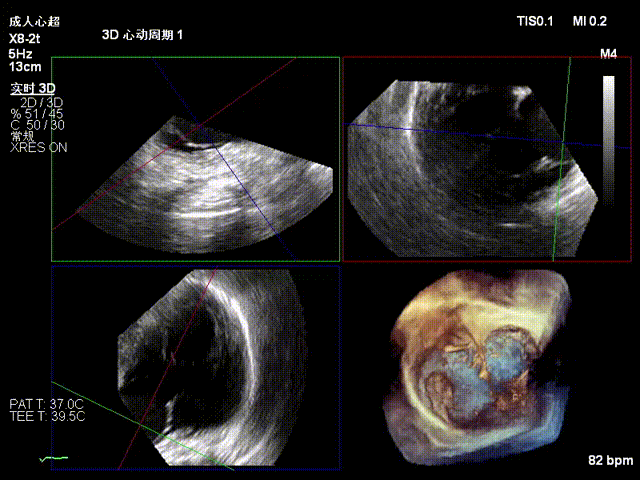

Postoperative regurgitation